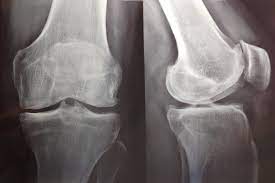

este nuevo análisis del estudio PRGF no encontró ningún beneficio clínica o estadísticamente significativo del plasma rico en factores de crecimiento (PRGF) en comparación con el ácido hialurónico. La restauración del Estudio PRGF muestra la urgencia de cambios importantes en las prácticas de supervisión e informes de juicios. En el futuro, se necesita acceso oportuno a todos los documentos de ensayos clínicos para minimizar el riesgo de sesgo de informe. Del mismo modo, los comités de ética deben estar listos para intervenir cada vez que surja un caso de posible mala conducta. Trials, 18 de enero de 2023